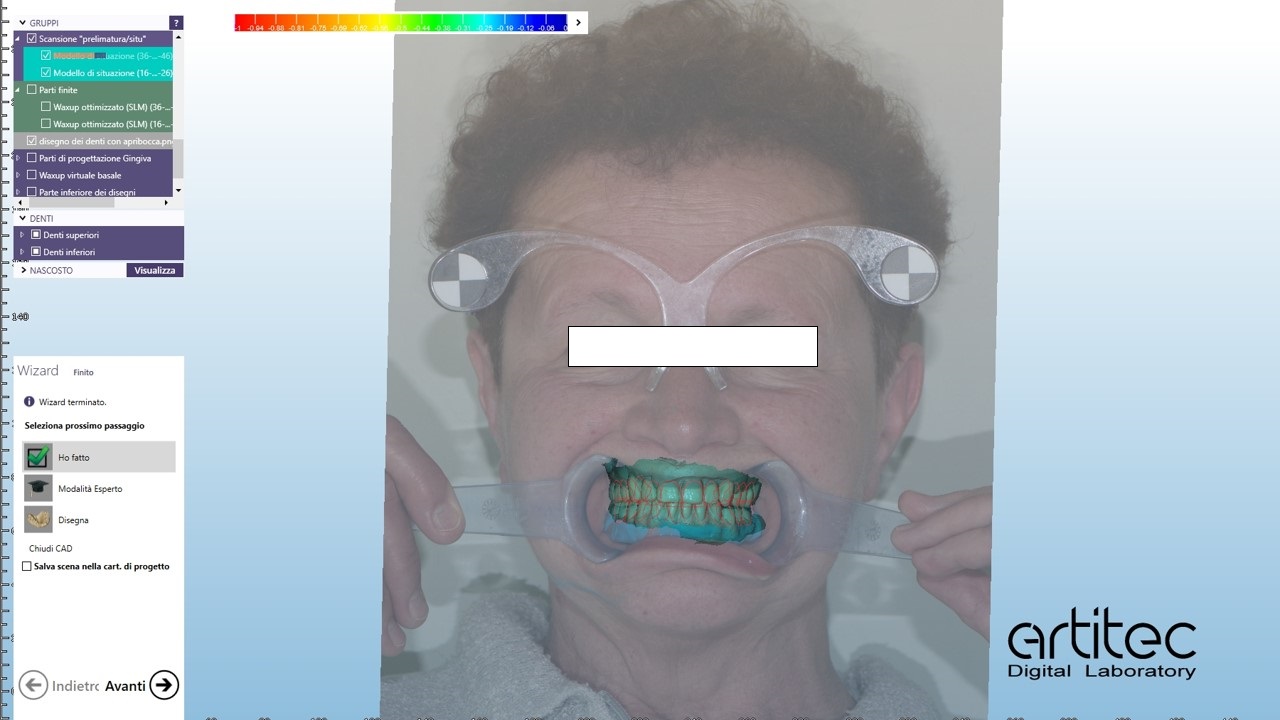

foto 13 match tra scansioni e fotografia

La fase protesica inizia con la ribasatura delle protesi provvisorie per rilevare la corretta anatomia della cresta. Quindi si procede a scansionare con scansione intraorale le impronte ottenute fuori dal cavo orale, poi le protesi provvisorie ribasate ricollocate nel cavo orale e la loro occlusione. Infine, si scansionano le creste edentule dopo aver posizionato gli scan body per tecnica digitale per rilevare la posizione degli impianti. Per la pianificazione sono scattate delle fotografie intraorali ed extraorali per la definizione dei limiti perimetrali del volto al fine di poter eseguire la programmazione del caso tramite il software di previsualizzazione. Le scansioni così ottenute sono poi inviate al laboratorio per la realizzazione di un prototipo delle protesi in prova.